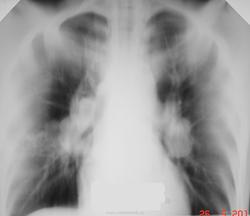

Пациент 22 лет, приехал работать из Средней Азии с намерением работать. Изменения в грудной клетке выявлены при проверочной (профилактической) флюорографии. Последняя флюорография в 2007 году во время службы в Армии. На контрольное обследования не вызывали. Временно проживает у родственников. В течение последних двух недель беспокоит постоянный сухой кашель, слабость. Объективно: пониженного питания, астенического телосложения, кожный покров чистый. В легких дыхание жесткое, единичные сухие хрипы. Тоны сердца ясные. ЧСС-72, АД 110/70 мм.рт.ст. Анализ крови прилагается. С уважением Nikolas

после постановки пробы Манту с 2ТЕ мы воскликнули, "О...." (см. рисунок). Срочно исследовали три пробы промывных вод бронхов на МБТ методом бактериоскопии. МБТ не обнаружили. С уваженим Nik

внутригрудных лимфатических узлов сегодня. Такие формы описаны в период блокады Ленинграда во время ВОВ. Хотел многое написать по этому больному, но не буду коллеги Вас утомлять. Примите к сведению, что такие двусторониие процессы могут быть и в Вашей практике. При бронхоскопии выявлен активный туберкулез в долевых бронхах; в промежуточном бронхе - бронхолимфатический свищ. Посевы бронхиальных смывов дали рост МБТ, чувствительных ко всем противотуберкулезным препаратам. Больной после окончания обследования уехал домой к родителям. Мы сами, в первую очередь, думали о саркоидозе. Спасибо Вам за активное участие. С уважением ко всем Nikolas.